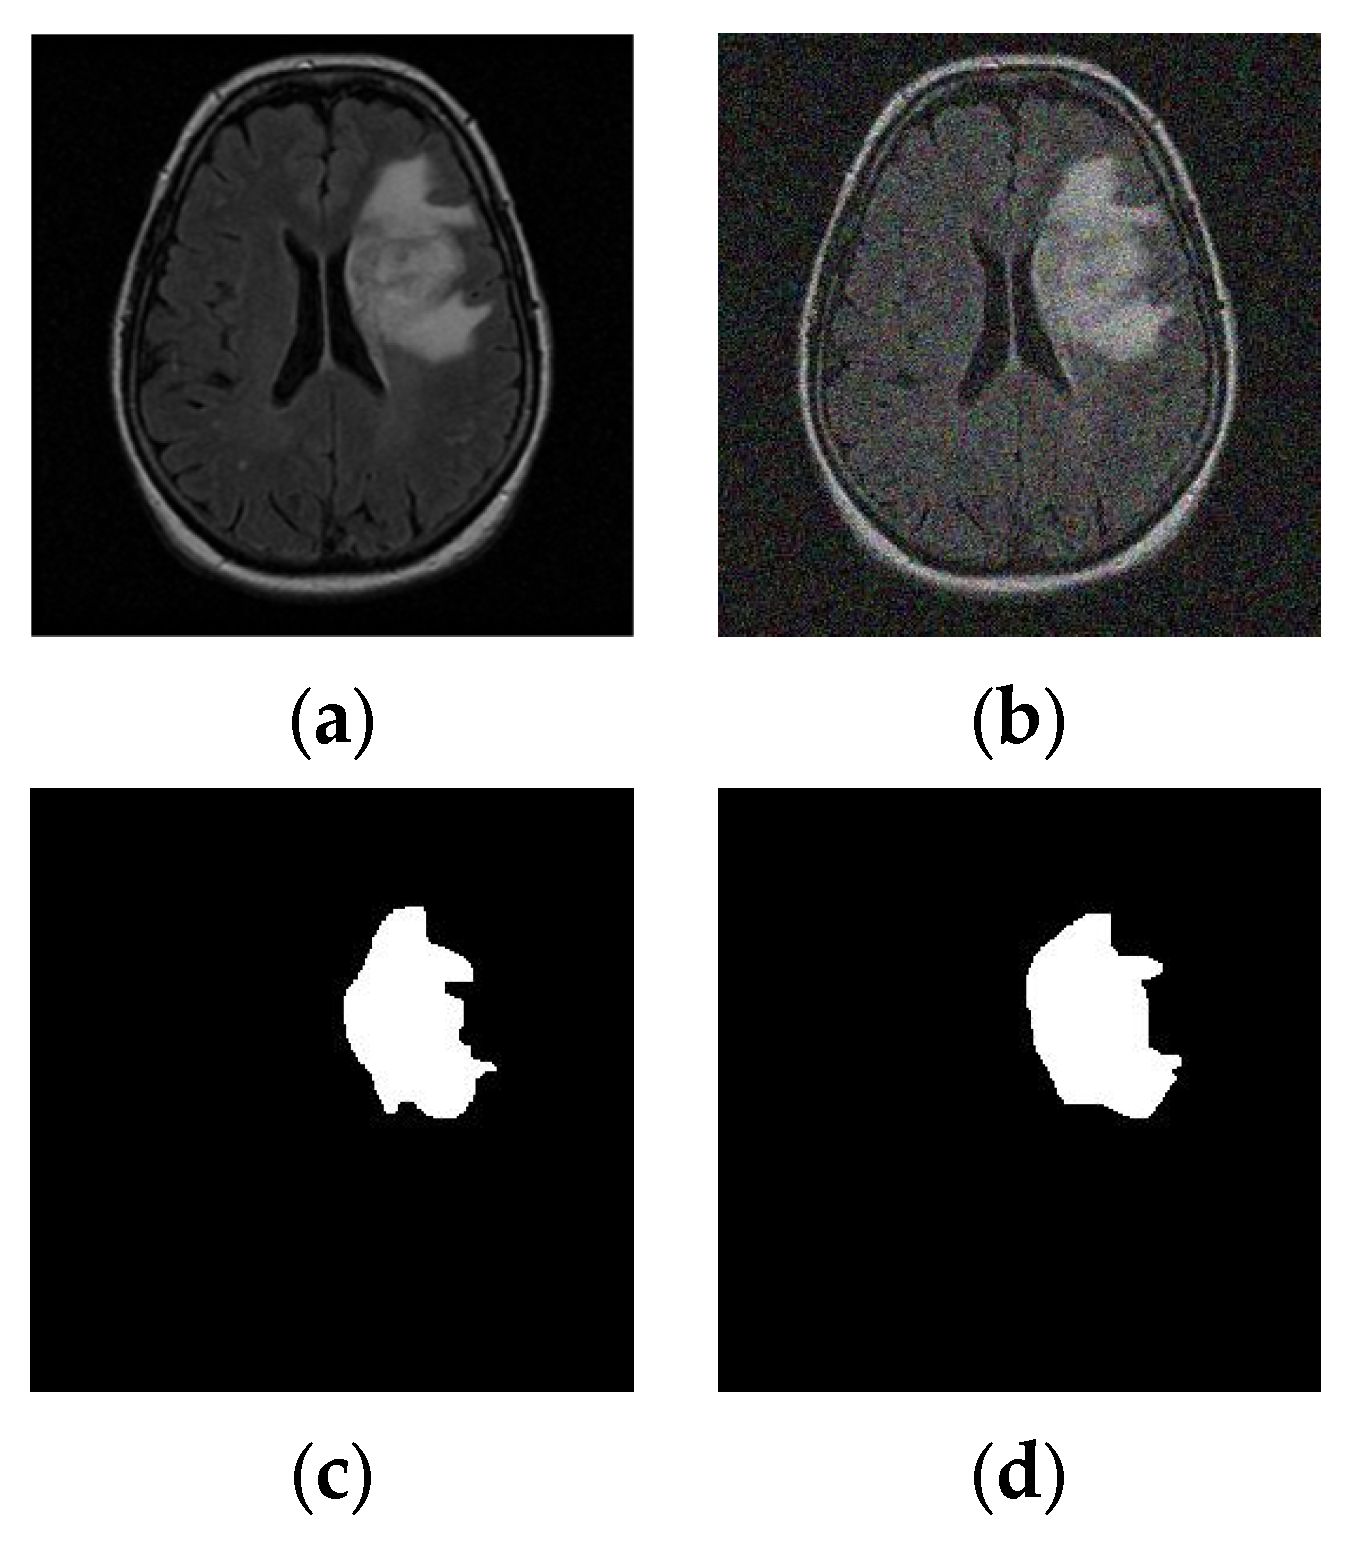

3.3.2. Tumor Features